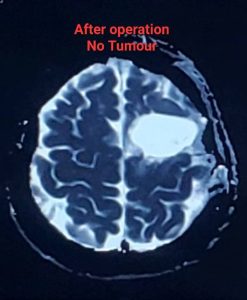

লো-গ্রেড গ্লিওমা সার্জারির পর prognosis বেশ ভালো হতে পারে, বিশেষ করে যদি টিউমার সম্পূর্ণ বা বেশিরভাগ অংশ অপসারণ করা যায়। গবেষণায় দেখা গেছে, দ্রুত এবং কার্যকরী সার্জারি জীবনকাল বাড়াতে এবং খিঁচুনি নিয়ন্ত্রণে আনতে সাহায্য করে। যদিও লো-গ্রেড গ্লিওমা সাধারণত ধীর গতিতে বৃদ্ধি পায়, তবুও এটি সময়ের সাথে সাথে উচ্চ-গ্রেডে পরিবর্তিত হতে পারে। তাই নিয়মিত ফলো-আপ এবং প্রয়োজনে অন্যান্য চিকিৎসা,যেমন – রেডিয়েশন থেরাপি বা কেমোথেরাপি, অত্যন্ত গুরুত্বপূর্ণ।